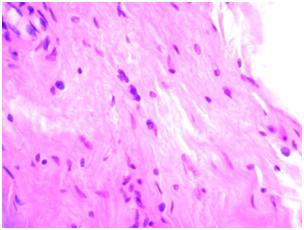

Lyophilized bovine pericardium - was presented as a narrow strip of connective tissue, mainly cell-free substance with no surface epithelium. Somewhere deep in the foundations were examined some fibroblasts with an elongated nucleus and clear cytoplasm. There were no signs of inflammation (Figure 1). When the preparations were stained with hematoxylin and eosin, it was easy to clearly distinguish the fibrous structure of the tissue.

Figure 1 Single fibroblasts in the thickness of the pericardial leaflet. Stained with hematoxylin-eosin, uv.400.